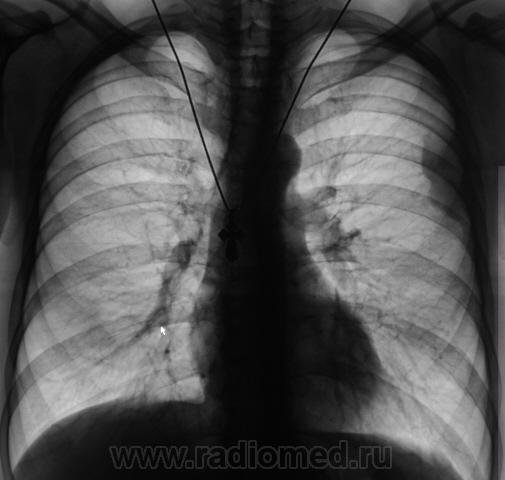

Снимки, 2 недели тому, перед отправлением пациента в "Главную областную тубарскую контору".

1.P5310038.JPG2.P5310039.JPG

Ну это кардинально меняет суть дела....2 недели назад было другое...Шалят плевриты - то тут, то - там....

Следовательно - Виталий был прав (Виталий Орестович, снимаю шляпу!!!).

С учетом упорного течения, был заподозрен специфический плеврит. Вместе со снимками были произведена и томограммы.

Спасибо. Могу добавить что последний год отмечаем рост частоты плевритов.

В "Главной конторе" в последний раз был "установлен" туб. плеврит, были найдены "палки", официально было назначено специфическое лечение. Но до этого Главная контора отвергала специфический плеврит. Ниже приводятся снимки, с которыми ранее пациент направлялся в "тую" контору.